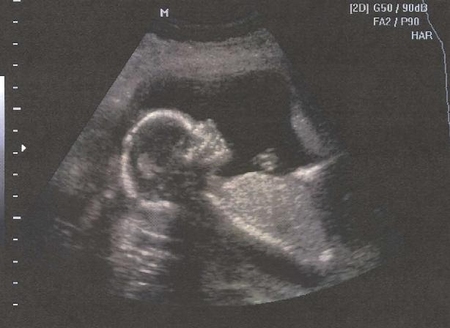

Узи № 3 (он же 2-й скрининг)

Делала в ЦИРе, с фотками и видео. Врач попалась молодая, но приятная и, по-моему, опытная девушка. Очень долго и тщательно все проверяла, измеряла, показала все в деталях :) И, наконец, мы узнали пол! Ждем мы девушку-красавицу!

Самое главное, что дочурка развивается по всем нормам, никаких отклонений не обнаружено! Чему я особенно рада!

По результатам узи мы всего на 2 дня опережаем акушерский срок.

А вот, кстати, и виновница поста:

Девочка-принцессочка это так здорово!!! Такая лапочка на второй фотке, где профиль так отлично получился!